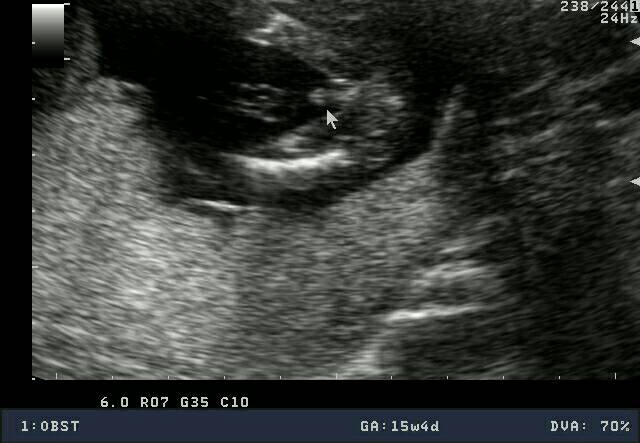

Badania, Wizyty, USG :)

• 1452020736294.jpg

1452020736294.jpg

36,6 KB · Wyświetleń: 98